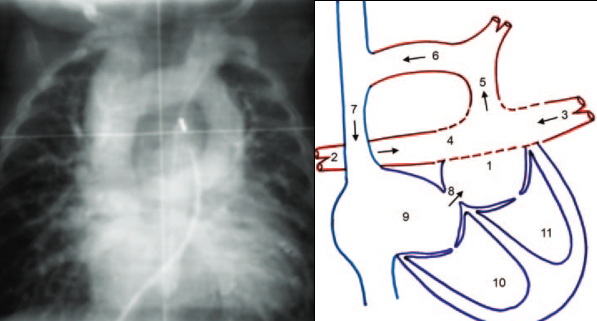

PAPVR

Partial Anomalous Pulmonary Venous Return

- Une ou toutes les veines pulmonaires DROITES se connecte hors de l’OG

- Signe du cimeterre

- Le Syndrome du Cimeterre se définit par:

- PAPVR

- Hypoplasie pulmonaire droite (pneumonies à répétition)